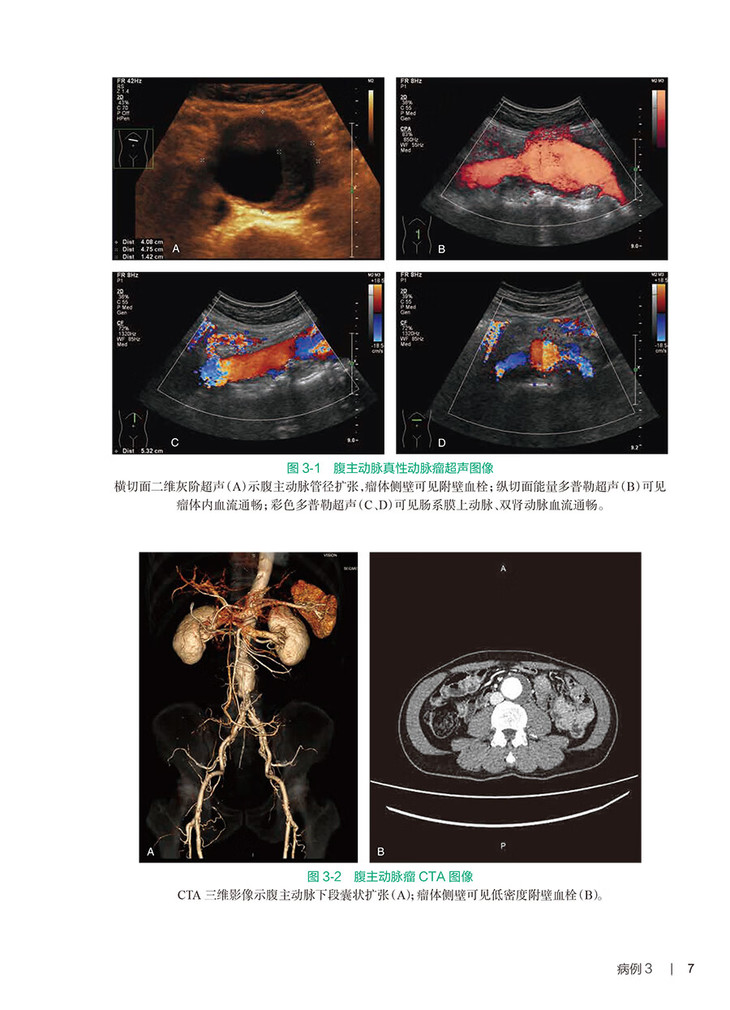

腹部血管影像特征与腹部疾病及全身血管病变密不可分,而超声检查相对其他影像检查更加便捷、实时,希望通过100例典型病例,结合病史、临床表现,通过临床思维引导超声医师检查思路和从临床角度进行图像解析。腹部血管疾病典型超声图解100例,包括腹部动静脉系统疾病,其中包括肾动脉疾病肾血管超声造影与DSA和CTA成像比较,腹主动脉支架术后瘘造影评估、下腔静脉等造影检查等精彩病例展示,有完整病例呈现及辅助其他影像检查DSA\CTA图像,及在临床治疗和随访过程中的超声动态改变,呈现一个完整的、有新技术应用的腹部血管疾病超声典型病例解析。